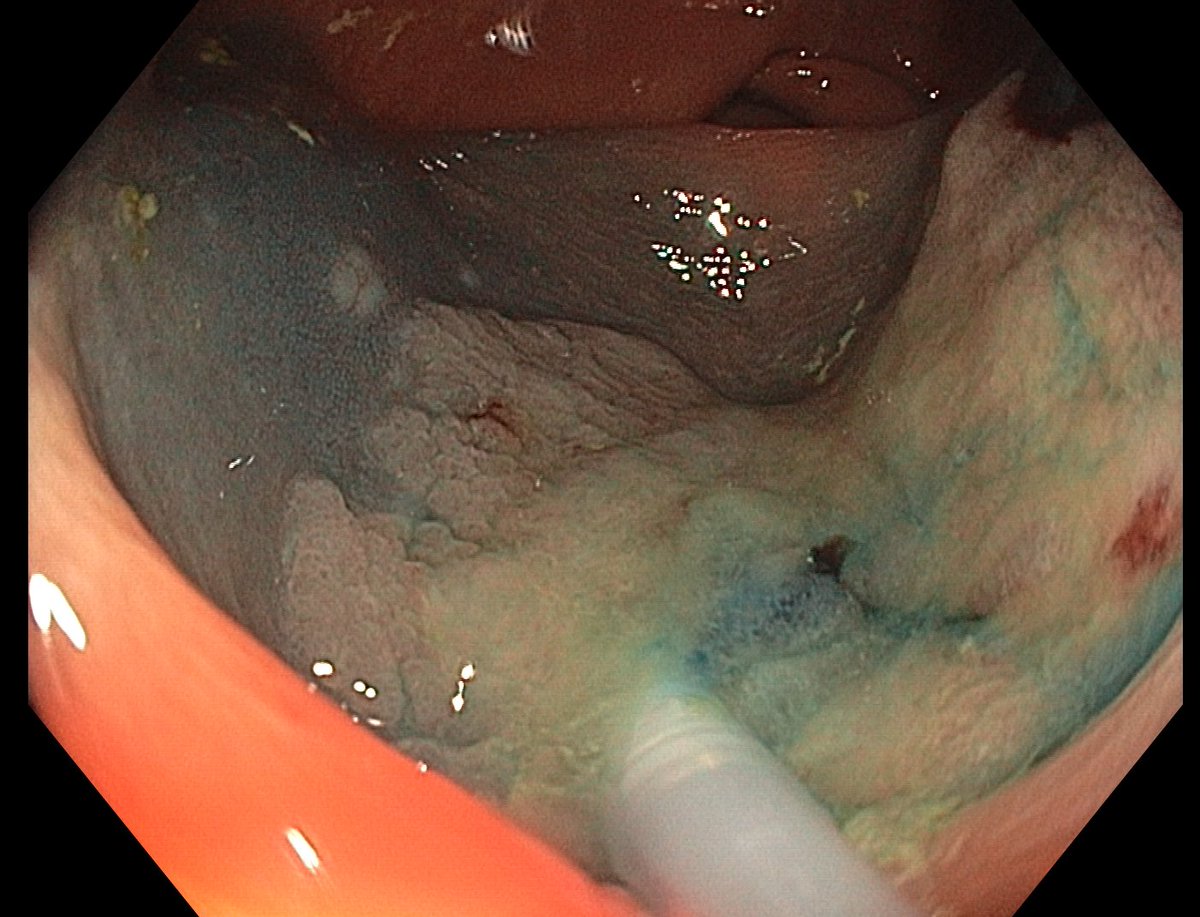

📢 March 2026 Issue #ACGCRJ 📷: Endoloop assisted hot snare polypectomy of a large brunner gland hamartoma in distal duodenum using colonoscope.🔦 🔗journals.lww.com/acgcr/pages/cu… @DushDahiya @DaniyalAbbasMD @AmCollegeGastro

This lesion was diagnosed in the distal sigmoid colon? What do you do next?